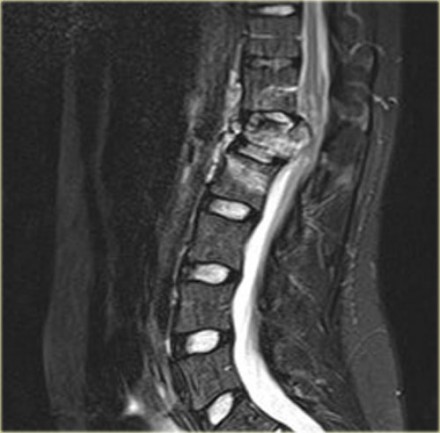

The images are of a patient with a typical bamboo spine as a result of ankylosing spondylitis.

After a fall on his back no fracture was seen on the x-rays.

However the CT shows a thin fracture line through the anterior side of the vertebral body and also through the spinous process.

Continue with the MR-images.

Look at the images.

What are the findings?

Then scroll to the next images.

The findings are:

- Vertebral bodies show marrow edema as a result of a fracture.

- Torn flaval ligament (yellow arrow).

- Fractures through the posterior elements (red arrows).

The TLICS-score is high, because there is distraction and injury to the PLC.